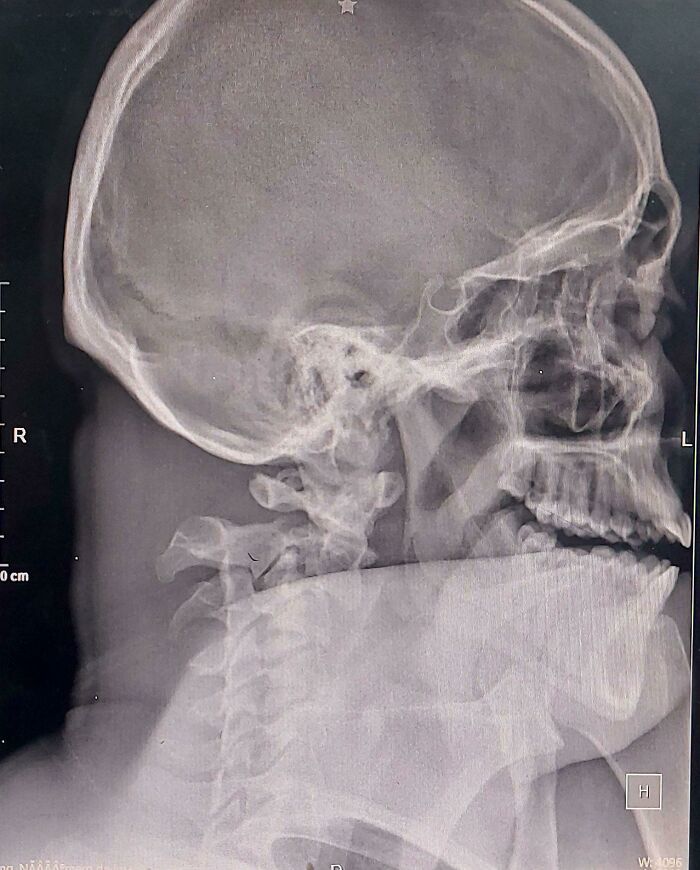

Этот мужчина самостоятельно приехал в отделение интенсивной терапии на такси

Даже если вы не уметет читать рентгеновские снимки, вам всё равно очевидно, что с шеей у него, мягко говоря, что-то не так.